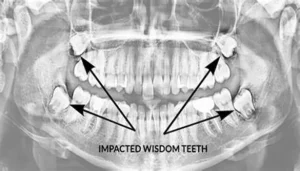

Wisdom teeth are the third set of molars at the back of the mouth, and they usually emerge between the ages of 17 and 25.

Wisdom teeth removal is a common dental procedure, often performed when these third molars are impacted, causing pain, infection, or alignment issues. After the surgery,